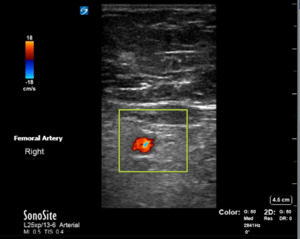

Bedside ultrasonography confirmed a large hematoma with heterogeneity in the popliteal fossa extending superiorly into the distal femur and inferiorly into the calf. While the femoral artery was found without anomalies on ultrasound, no popliteal artery could be found in the popliteal hematoma (Figures 3 and 4). This was concerning for active bleeding in the popliteal fossa from damage to the artery.